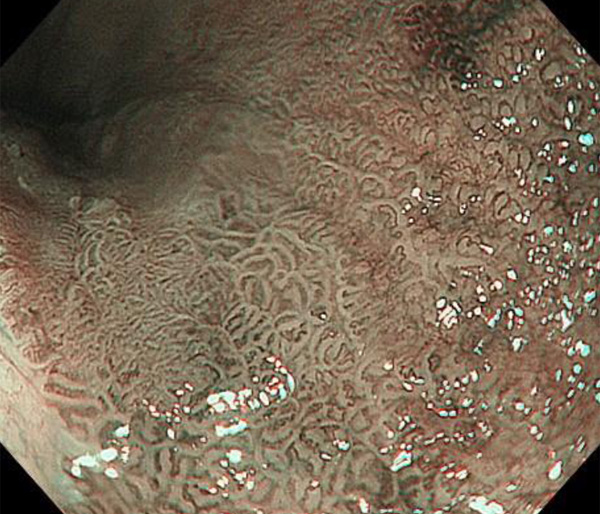

内視鏡所見と病理組織像の1対1対応が可能な症例を公募いたします。主にLSBEに発生した早期癌(HGDを含む)を対象としますが、興味深い症例であればSSBE癌でも結構です。採否は世話人へご一任ください。

症例呈示希望者は応募用紙に記入の上、代表的な内視鏡(2枚)、切除標本(新鮮、固定)、切り出し図、マッピング、代表的組織像とともに、Barrett 食道研究会事務局 barrett.shinshu@gmail.comへお申し込み下さい(10MB以下でお願い致します)。

特に、本邦では極めて稀なlong segment Barrett’s esophagus(LSBE)から発生した早期癌は、診断に難渋する場合も多く、欧米ではランダム生検による検出が標準的とされています。背景のBarrett食道もろとも全体を内視鏡切除+ラジオ波焼灼する欧米と異なり、ESDで内視鏡的な局所切除が基本の本邦では、存在診断+範囲診断(特に水平)を的確に行うことが不可欠です。

そのためには、一流の病理医による組織学的診断とエキスパート内視鏡医による拡大内視鏡像との一対一対応を徹底的に行うことで、『本来、見えないであろう拡大所見の先にある組織構築像が診えてくる』所まで内視鏡診断レベルを上げていく必要があります。その実現には、一対一対応を追究した症例(特にLSBE発生例)1例でも多く経験するしかありません。本研究会でBarrett食道腺癌(LSBE発生早期病変)を共に学び、拡大内視鏡像の一歩先を診るスキルを習得しましょう!一人でも多くの皆様のご参加をお待ちしています。